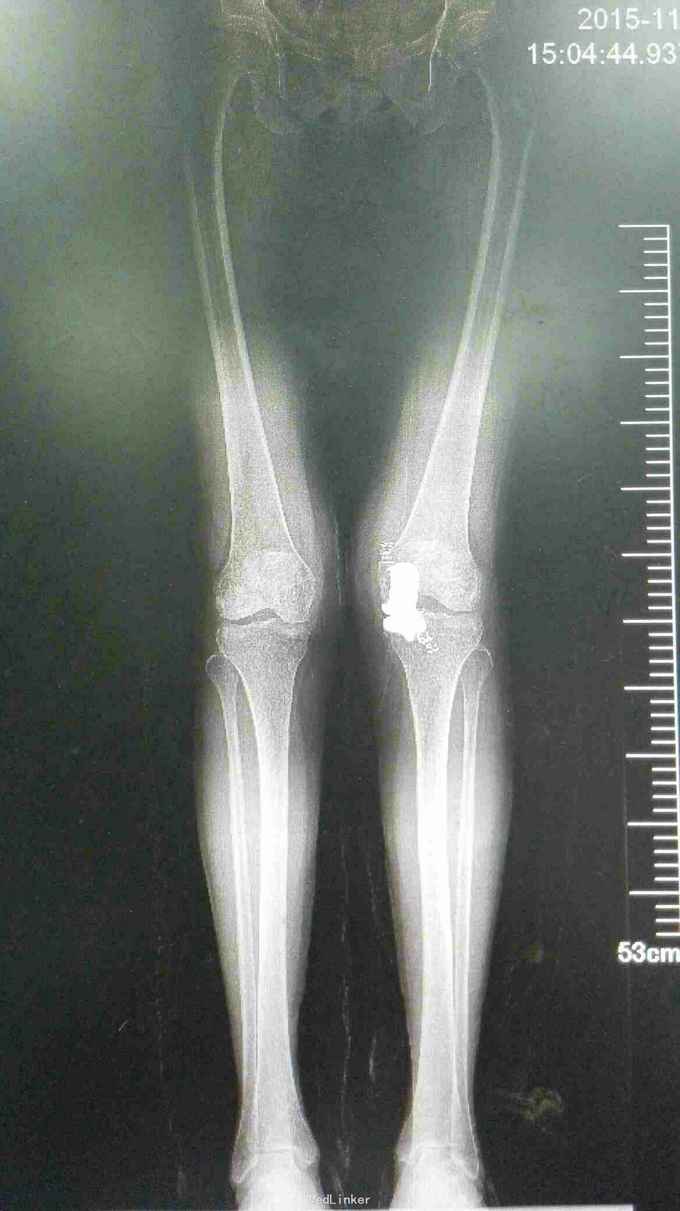

76岁女性,左膝关节疼痛5年,加重1月。平时以活动痛为主,最近一月疼痛明显,影响行走。既往体检。

左膝轻度内翻畸形,皮温稍高,膝关节前内侧压痛阳性,内外侧方应力试验阴性,前后抽屉试验阴性。屈伸活动度0---110度。 入院辅助检查:血常规、ESR、CRP、PCT均在正常范围。心肺功能可。

诊断:左膝关节骨性关节炎 治疗:左膝关节单髁置换术

术后第一天下地,1周出院,出院时屈伸活动度0---110度 讨论:虽然患者年龄大,但病变局限于单间室,行单髁置换仍未较合理选择,手术创伤小,恢复快。术前备用了全膝置换器械,如果前交叉韧带断裂需行全膝关节表面置换术。